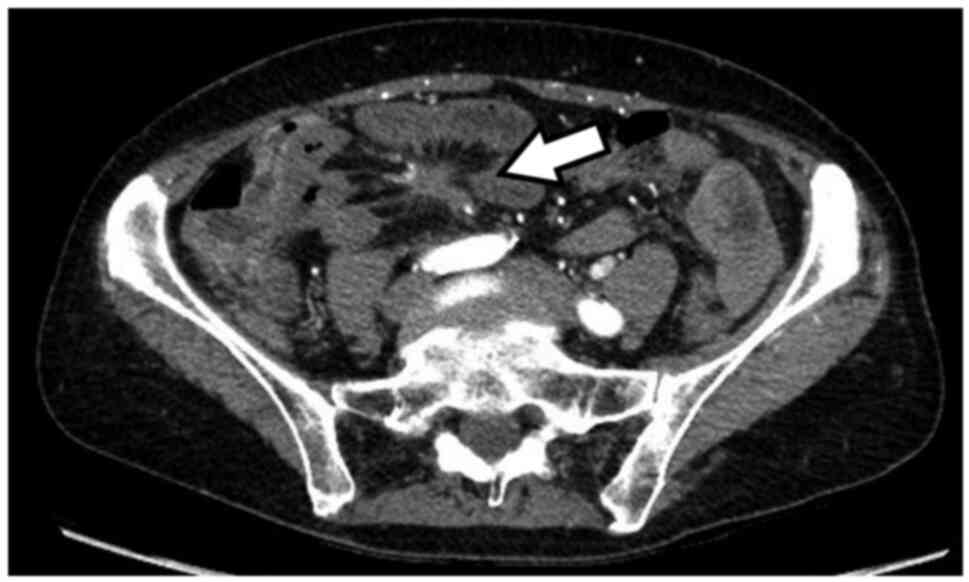

A 68-year-old Caucasian female, with no remarkable medical history, presented herself at AZ Sint-Jan (Bruges, Belgium) in April 2017. She was referred to us because of altered defecation in association with lower abdominal cramps, and significant weight loss despite normal appetite. A CT scan of chest and abdomen revealed multifocal liver metastasis and a characteristic cartwheel at the level of the mesentery, suggestive of neuroendocrine origin (Fig. 1). Patient's basic laboratory values were normal. Serum chromogranin was raised at 39,300 mcg/l. Further imaging with 68Ga-DOTATATE PET-CT identified the mesenteric cartwheel lesion lacking SSTR expression, a focus with increased somatostatin receptor expression in the middle section of the ileum, diffuse liver metastasis and lymph nodes in the right inguinal region with high SSTR expression. No other lesions suspected for a primary tumor site outside the ileum were detected. On endoscopic ultrasound, no primary pancreatic lesion was identified. A core biopsy of one of the liver lesions confirmed the neuroendocrine origin with a Ki67 index of less than 3%. Because of sub-obstructive symptoms, the patient was sent for surgery. On histomorphological and immunohistochemical analysis of the oncologically resected ileal segment a G1 NEN with Ki67 index 1%, without clear mitosis, and with pronounced perineural and vascular invasion was diagnosed. The investigated lesions were found within the ileal mesenteric fat (Fig. 2) and not in the wall of the provided transverse ileal sections. Two out of 5 lymph nodes were positive for metastatic involvement, with capsular invasion in one of them. The multidisciplinary oncology board confirmed the diagnosis of siNEN and a treatment with lanreotide was initiated at 90 mg on a monthly basis. During the following year, the patient started losing weight and periodically had mild symptoms of intestinal obstruction with a spontaneous resolution after a mean of 3 days. Chromogranin remained globally unchanged. One year later, the patient presented to the emergency department with bowel obstruction. A CT scan revealed disease progression with de novo peritoneal implants, ascites, an increased number of liver lesions, with central necrosis in some of them. Serum chromogranin raised from 7,320 mcg/l (value after segmental ileal resection) to 22,600 mcg/l. Symptoms resolved on supportive therapy. A 68Ga DOTATATE PET-CT was repeated, revealing clinically evident small bowel sub-obstruction as well as omental carcinomatosis, an implant in the right iliac fossa as a new finding, and progression of the liver metastases. A 18FDG PET-CT was planned and an exploratory laparoscopy was performed. The histomorphological examination of one of the peritoneal tumor nodules revealed lympho-vascular invasion and a Ki67 index of 2% (Fig. 3). Consequently, the dose of the octreotide analogue was augmented to 240 mg monthly. Peptide receptor radionuclide therapy (PRRT) and everolimus were not considered a valid therapeutic option after multidisciplinary consultation. 18FDG PET-CT did show a hazy infiltration of the mesentery, but no avidity in the liver lesions, and no pulmonary or osseous lesions. Three months later the patient presented once again to the emergency department with malaise, nausea, vomiting, and abdominal tenderness. Blood analysis showed an acute renal insufficiency and significantly raised inflammatory parameters (CRP 441 mg/l). On urgent CT scan an intestinal perforation was obvious. The patient underwent an emergency laparotomy which uncovered an inoperable state of bowel obstruction with necrotic small bowel segments and diffuse tumor invasion. Shortly after the intervention she developed sepsis. In agreement with the family as well as the medical team, life support was withdrawn, and the patient passed some hours later.

Figure 1

CT scan. Cartwheel lesion at the level of the mesentery (arrow).